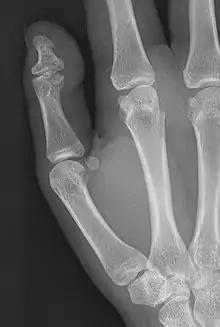

Brachyphalangy of the thumb's distal phalanx, also known as brachydactyly type D, with otherwise normal phalanges of the 2nd-5th digits

Brachyphalangy of the distal phalange of the thumb

This condition is caused by either fusion or early closure of the phalange's growth plate. One example is brachydactyly type D, which is caused by an early closure of the thumb's distal phalange, leading to a congenitally short thumb with a similarly short and wide thumb nail.